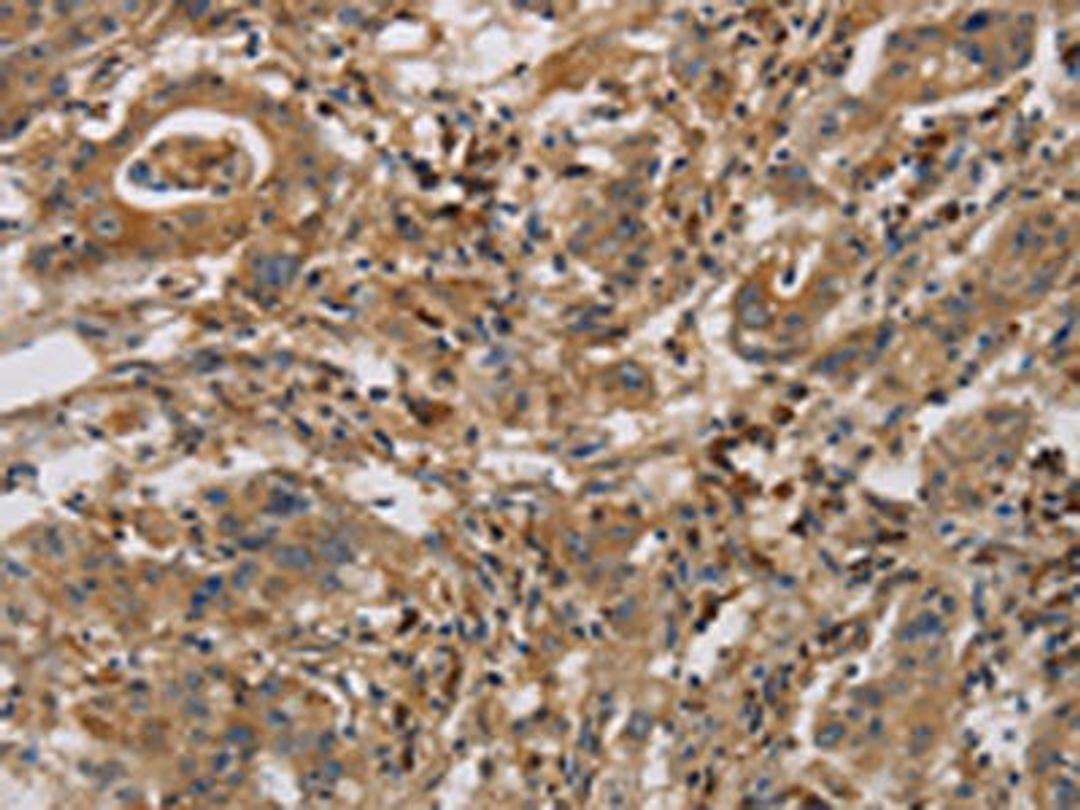

Product & ReviewsAntibodiesCASP9 AntibodyProduct DetailsCat. No.CSB-PA785649TypePrimary AntibodyClonalityPolyclonalHostRabbit0.0/5.0|0 Reviews|Write your own ReviewThe image is immunohistochemistry of paraffin-embedded Human gastric cancer tissue using CSB-PA785649(CASP9 Antibody) at dilution 1/70. (Original magnification: ×200)ReviewsSpecificity rating Sensitivity rating Quality rating Be the first to leave a reviewApplications ELISA (ELISA) Western Blotting (WB) Immunohistochemistry (IHC)Antibody OverviewCASP9 Antibody0.0/5.0|0 Reviews